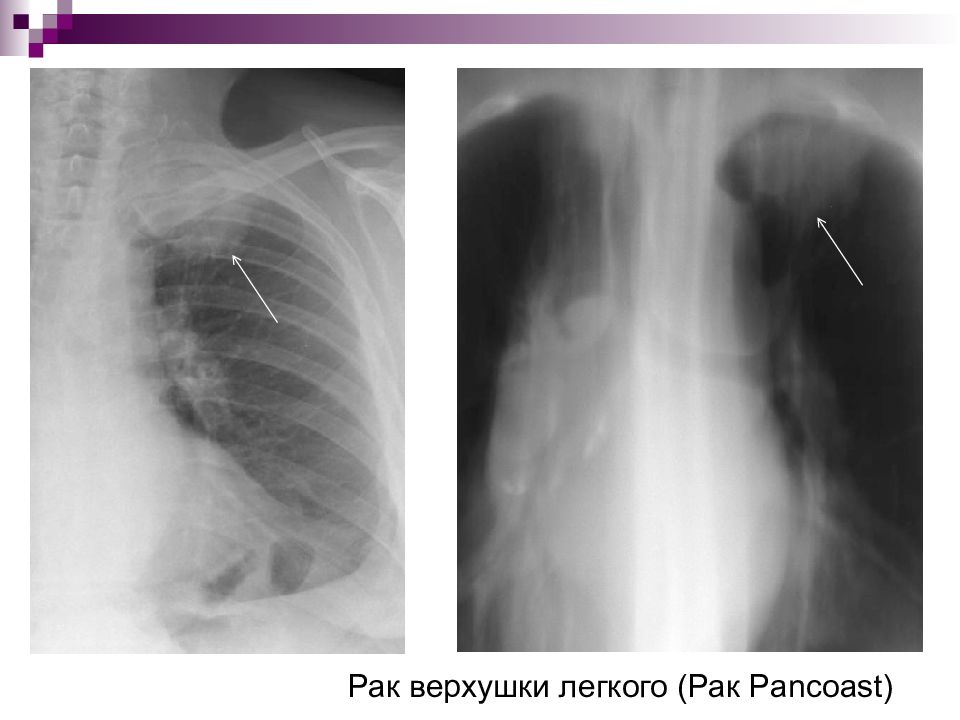

Рентгеновские снимки опухоли Панкоста